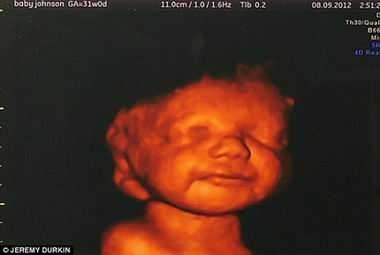

- 孕妇产检看到腹中残疾胎儿微笑 决意不堕胎(图)

- 时间:2013-01-16 19:25:19